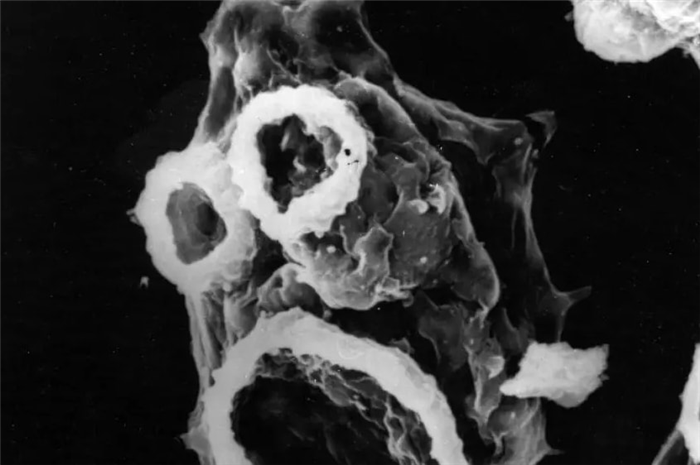

На снимке: мозг человека, пораженный амёбой Неглерии Фоулера.

При вскрытии наблюдается выраженный отек головного мозга , гиперемия мозговых оболочек с возможным наличием гнойного экссудата в бороздах у основания мозга и мозжечка ; повреждение спинного мозга непостоянно. Из кист амебы присутствуют в большем или меньшем количестве в спинномозговой жидкости и субарахноидальном экссудате (см. Мозговые оболочки ). Он обнаруживается в периваскулярном кластере в пространствах Вирхова-Робена или в сером веществе, но очень редко в белом веществе (см. Нейроанатомия ).

Амебный менингит вызывает поражение нервных клеток, некроз мозговых оболочек, отек и гипертермию мозга, вокруг луковиц образуется гнойный экссудат. Амеба Неглерия Фоулера начинает активно размножаться, питаясь клетками мозга, поэтому без своевременного лечения менингит приводит к летальному исходу пациента.